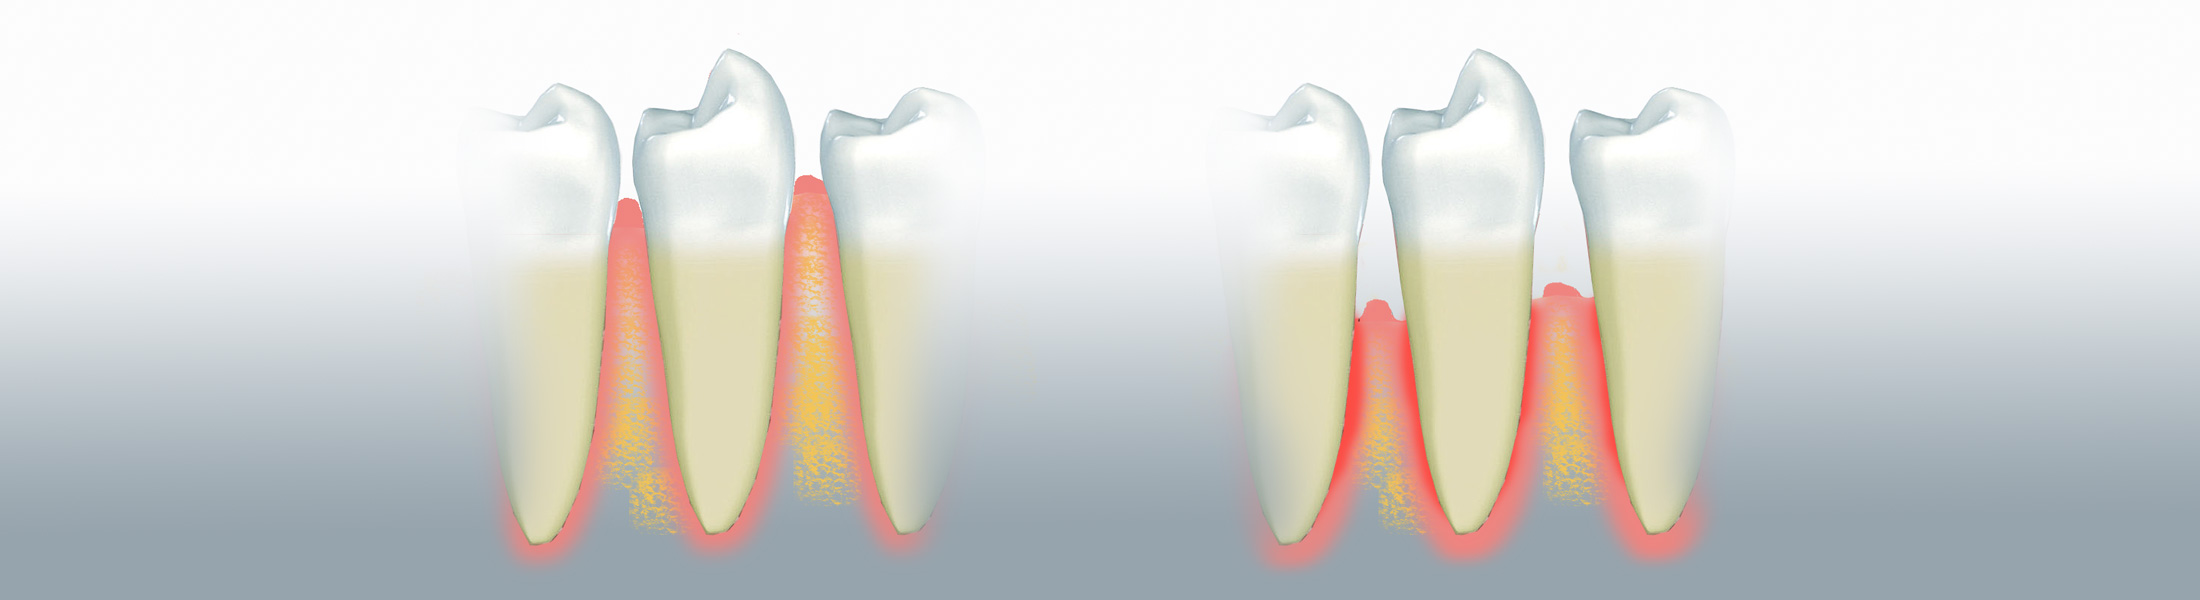

Die modernen Techniken der Parodontologie ermöglichen eine wirksame Behandlung der Parodontitis. Die Parodontitis ist eine entzündliche Erkrankung des Zahnhalteapparats. Sie wird durch Bakterien verursacht, die sich zwischen Zahn und Zahnfleisch ansammeln.

Die bakterielle Infektion muss als erstes behandelt werden. Deshalb beginnt die Therapie mit der Einweisung in die häusliche Mundhygiene sowie der Hygienephase mit professioneller Zahnreinigung in unserer Praxis. Als erstes werden die Zahnfleischtaschen und Wurzeloberflächen gründlich unter örtlicher Betäubung (örtliche SchmerzausschaltungLokalanästhesie) gereinigt. Mit speziellen Instrumenten entfernen wir die tief unter dem Zahnfleisch auf den Wurzeln der Zähne haftenden, harten Beläge und glätten die Wurzeln (Kürettage). Gewebeschonendere Methoden ermöglichen es, auch tiefere Zahnfleischtaschen zu säubern. Primäres Ziel der Initialbehandlung ist die Entfernung der Keime, die die Erkrankung verursachen.